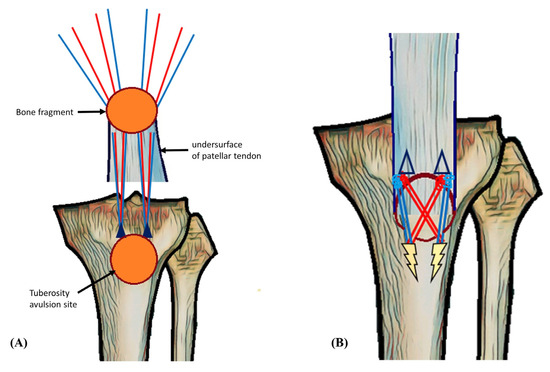

Isolated Avulsion Fracture of the Tibial Tuberosity in an Adult Treated with Suture-Bridge Fixation: A Rare Case and Literature Review

2. Case Presentation